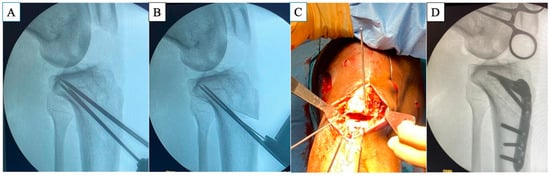

2.4. Radiographic Measurements and Clinical Outcomes